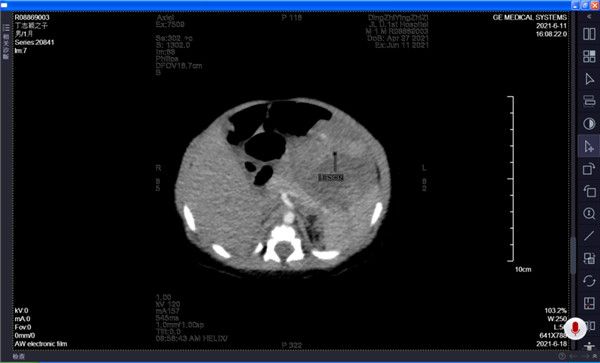

入院后,新生儿科组织多学科会诊,请儿外科及小儿肿瘤科共同制定孩子的诊疗方案。完善腹部彩超,CT三期增强及血管重建,PET-CT,HCG及AFP等相关检查后,医疗团队考虑肿瘤来源于肝脏左外叶,现已合并瘤内出血导致患儿贫血,应积极治疗。因瘤体较大有破裂出血危及生命的可能性,同时不除外肝母细胞瘤(恶性),所以尽早手术完整切除肿瘤成为治愈该患儿的首选方法。儿外科与放射线科、儿科彩超室反复沟通,仔细评估患儿影像学资料,认为患儿肿瘤发现早,PRETEXT分期I期,距离重要血管有足够间隙,术后剩余肝脏可以完全代偿,预估手术无残留(COGI期)无需二次手术,符合我国2019年版初诊手术切除儿童肝脏肿瘤的指征。6月22日,儿外科董春钰主任、赵继学副教授、徐阳主治医师手术团队在麻醉科及手术室的大力配合下,经过近2小时手术,将肿瘤完整切除,术中出血6毫升。术后病理回报:肝婴儿血管内皮瘤,经I期手术完整切除,患儿已临床治愈出院。